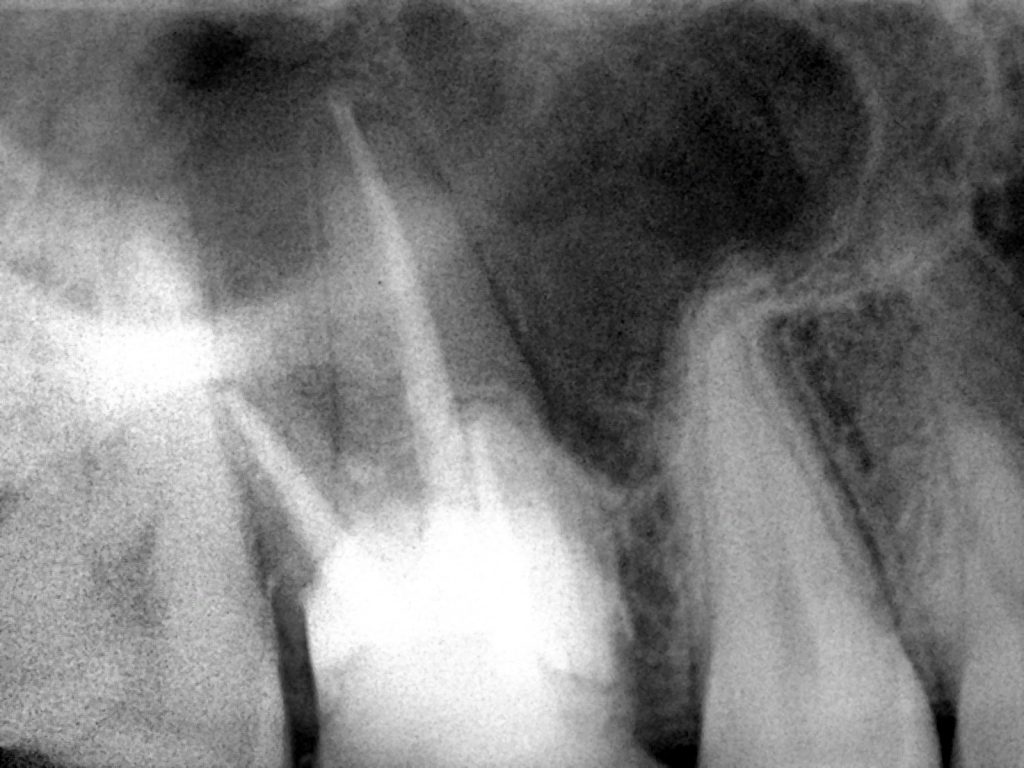

بعد التشخيص بالأشعة السينية والأشعة السينية

لقد أظهرت نتائج سيئة وقنوات متكلسة

Preoperative x-ray

Post operative x-ray after r.c.t done